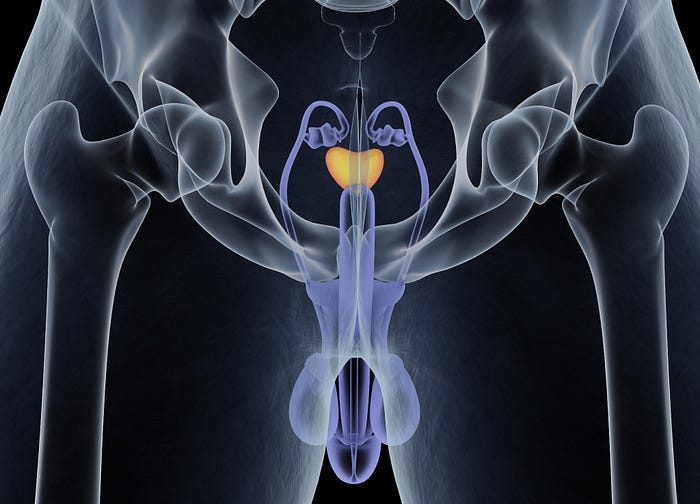

Understanding the Prostate: Dr. Gupta begins by providing a concise overview of the prostate, a walnut-sized gland that plays a crucial role in male reproductive health. He explains its functions, emphasizing the significance of early detection and preventive measures in maintaining prostate health.

Common Prostate Problems: The article explores prevalent prostate issues, including benign prostatic hyperplasia (BPH), prostatitis, and prostate cancer. Dr. Gupta discusses the symptoms, risk factors, and potential impact on quality of life, underscoring the importance of regular check-ups and screenings.

Screening and Early Detection: Regular screenings, including prostate-specific antigen (PSA) tests and digital rectal exams (DRE), are essential components of proactive prostate health management. Dr. Gupta provides guidance on when and how often these screenings should occur, stressing the importance of early detection for successful intervention.

Treatment Options and Patient Education: For those already facing prostate issues, Dr. Gupta discusses various treatment options available, ranging from medications to surgical interventions. He emphasizes the importance of patient education, ensuring individuals are actively involved in decisions regarding their treatment plans.